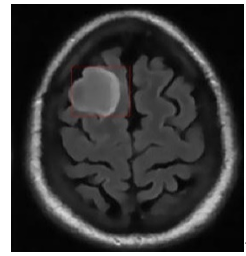

By using the same parameter configuration and initial contour as in the MATLAB simulation, we implemented the DRLSE method on the FPGA. The visual results, shown in Figure 13, demonstrate the algorithm’s effectiveness in segmenting medical images.

Initial contour

Segmented image

Figure 13. Result of implementing the DRLSE method

The implementation of the DRLSE algorithm on FPGA demonstrated satisfactory segmentation accuracy, with a rigorous visual comparison to the results obtained through MATLAB simulation [20]. No significant differences or errors were observed in the contours generated from the ϕ function.